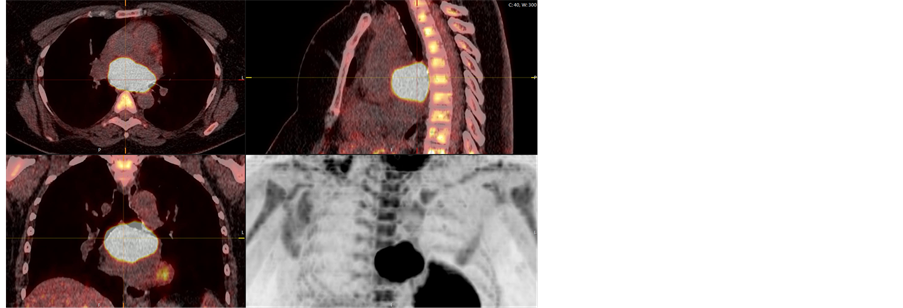

A Caucasian, overweight female patient, 42 years old at the time of referral, consulted her family doctor because of intermittent fever, attacks of sweating, dyspnea and dull epigastric pain and also relapse of previously experienced back pain. She was a non-smoker and had no other significant medical history. Clinical check-up and blood test showed no evidence of an infectious disease. As one of the further investigations, a computed tomography (CT) of the chest and abdomen was decided, in order to exclude a pulmonary embolism. Surprisingly, a mediastinal mass of 6.6 × 3.9 cm in size was revealed. It was located in close contact to the tracheal carina and the left atrium. Some enlarged right hilar nodes were seen, but no other suspicious findings were documented. A magnetic resonance imaging (MRI) could not completely exclude an infiltration of the surrounding tissue and organs. Radiologically the mediastinal mass was considered highly suspicious for a lymphoma, other differential diagnosis were rather unlikely, but could not be completely ruled out at the time. For further assessment the patient was referred to our thoracic surgery department. Positron emission tomography/computed tomography (PET/CT) supported the suspicion of a lymphoma limited to that area, no other FDG-avid lesions were seen, neither in hilar or mediastinal lymph node stations, nor in regions expected for any primary tumors (Figure 1). Lymphoma limited to the mediastinum was the first differential diagnosis. Therefore, a diagnostic mediastinal lymphnode biopsy by right-sided thoracoscopy was decided in order to obtain a tissue biopsy and to definitely rule out metastatic disease. Histopathological investigations of the hilar and mediastinal lymph nodes were negative for lymphoma as well as for other malignancies.

Figure 1. Pre-operative PET/CT.